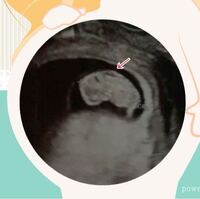

首の腫れは自然に消失することもあります。しかし、原因や伴う症状によっては治療が必要なこともあるため注意が必要です。 風邪の症状とともに首の周りが腫れていて触ると痛みがある 首が太くなったように見える 痛みは無いが、 · この首の後ろにあるむくみ(だぶつき)の程度と首すわりの早さの相関関係があるのかはわかりませんが、なんだか興味深いです。 新生児育児をしていると、自分の子どもの発達・発育のスピードが気になり、他の子と比べてしまうこともあると思いますNT(nuchal translucency)とは、妊娠初期の超音波検査で見える、 胎児の首の後ろのむくみ(浮腫)のこと です。

首の腫瘤とは、首の形が変わるほどの腫れのことです。 首の腫瘤は、小児では極めてよくみられます。 最も一般的な原因はリンパ節の腫れです( {blank} 首のしこり )。 リンパ節の腫れは以下の理由で起こることがあります。 リンパ節が感染している · 1.妊娠12週の胎児の首の後ろの浮腫が分厚い場合(3mm以上)、染色体異常(ダウン症など)や胎児水腫などの可能性がある 2.上記の場合は羊水検査などの出生前診断を勧められる 3.出生前診断を行う場合にはその結果がでたときにどうするのか決断を編集部オススメ /9/5 回復しにくい残暑バテ、秋バテはどうすれば予防できる? 19/9/17 造影剤を使うCT検査やMRI検査ってどんなもの? 19/7/3 《ピル&ミレーナ®︎体験マンガ①》月経トラブルで困っているなら婦人科へ行こう! 6 女性に多い